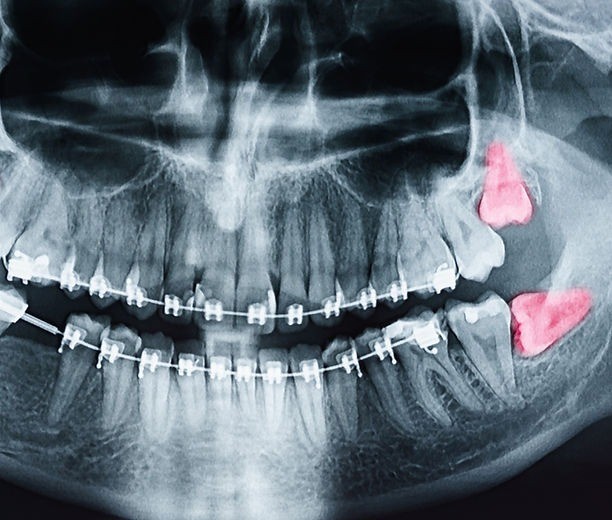

口腔外科では、親知らずの診断と治療を通して、将来的なお口のトラブルを防ぐことを大切にしています。親知らずは、正常に生えて咬合や咀嚼に関与している場合、必ずしもすぐに抜歯が必要になるわけではありません。しかし、15~16歳頃に生え始め、最も奥に位置する歯であるため、完全に生えきらず歯肉の一部に覆われた状態になることが多く見られます。

親知らずの周囲には、下顎の骨や下唇の感覚に関わる神経が走行しているため、抜歯は難易度が高くなることがあります。歯科口腔外科クリニックでは、お口の中の状態やレントゲン画像をもとに、安全性を最優先に診断を行っています。処置が困難と判断される場合には、口腔外科専門の医療機関へ紹介し、より専門的な治療へつなげています。